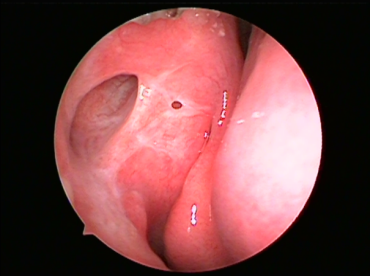

术后鼻内镜吻合口图片